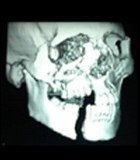

Facial trauma, also called maxillofacial trauma, is any physical trauma to the face. Facial trauma can involve soft tissue injuries such as burns, lacerations and bruises, or fractures of the facial bones such as nasal fractures and fractures of the jaw, as well as trauma such as eye injuries. It will depend on the type and extent of fracture and what other problems and treatment you had. Bruising and swelling usually takes 2 to 3 weeks to settle down. At this point, you will begin to look more normal. After this time the body will continue to heal itself inside.

Facial Trauma includes injuries involving the mouth, face and jaw. These range from facial cuts and lacerations to more serious problems, such as broken teeth and facial bones. Bone fractures can involve the lower or upper jaw, palate, cheekbones and eye sockets. These injuries often occur during automobile accidents, sports or recreational activities, fights or assaults, work-related tasks, projects around the house or accidental falls. Many patients with facial injuries are first seen in the emergency room and then referred to an oral and maxillofacial surgeon or a plastic surgeon for further treatment. Signs of Facial Trauma